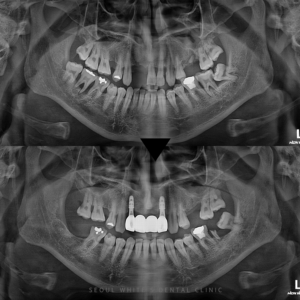

내원 당시 환자분은 윗니는 틀니를 사용 중이었고, 아랫니는 대부분 자연치였지만 전체적으로 심한 동요가 관찰되었습니다. 이 경우 치아를 억지로 살리는 것보다 예후가 나쁜 치아를 발치하고, 임플란트로 대체하는 것이 기능 회복에 훨씬 유리합니다.

정밀 진단 후, 잇몸뼈 상태를 확인한 결과 식립이 가능한 조건이었기에 디지털 가이드 수술을 계획했습니다.

치료 전에는 식사조차 어려워 하셨던 환자분은, 치료 후에는 건강한 모습으로 정기 검진을 받으러 오십니다. 아랫니 전체 기능이 복원되니, 발음, 저작력, 외모까지 동시에 좋아지는 변화를 경험하게 되었습니다!